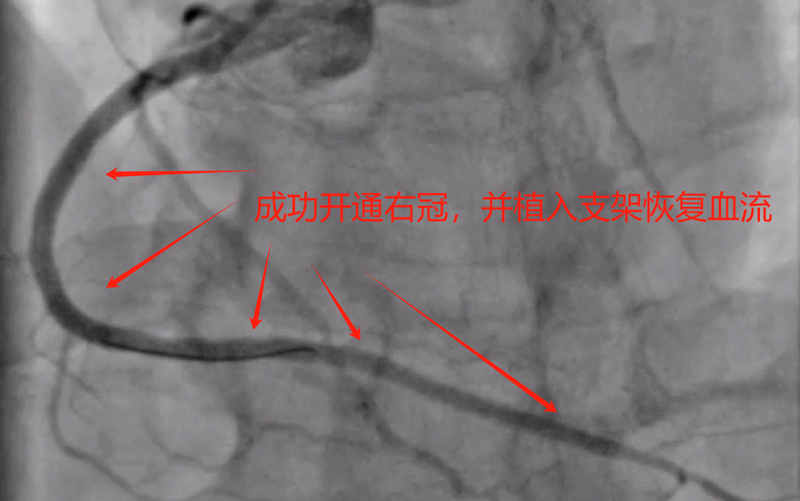

患者王某,男性,61岁,长期抽烟,本次因活动后气促入院,考虑冠心病导致心功能下降所致,经过治疗后,与家属及患者沟通后同意行冠状动脉造影。造影提示前降支、钝缘支及右冠均慢性闭塞,可见小血管侧支循环闭塞血管,冠脉病变极为复杂,获得家属同意后,来凤县人民医院心血管内科介入团队为患者制定了手术方案,先尝试开通右冠闭塞血管,择期尝试开通前降支闭塞及钝缘支闭塞血管。经过接近3小时努力,成功开通患者右冠闭塞血管,并联合IVUS成功植入支架,患者右冠血流恢复正常。

术后